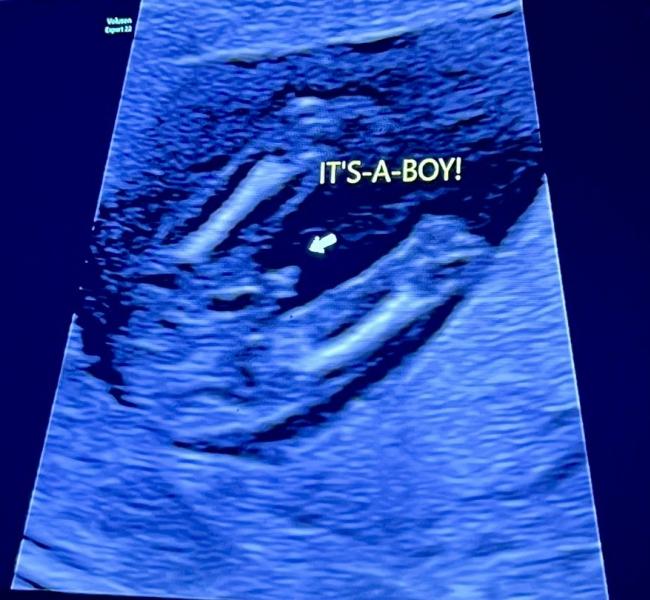

И на счет пола сказала увидеть скажет - но точно лучше на 2 скрининге , но чтобы вы понимали как датчик оказался между ног стоял просто смех в кабинете - невозможно было не увидеть ) девочки , у нас Мальчик 🥹💙 Аллахка Шукир 🙌

Да , все зависит от аппарата узи , фото приложила - писюн 100% никуда не денется сказала 🤣🤣🤣

Прием стоил 30.000 тенге первый скрининг, принимает она в цмм Рыскулова 5/1 , да она долго смотрела и прям тщательно . И в начале такая видно будет ок напишу , если нет нет - как датчик поставила мы все увидели писюн и начали громко смеяться 🤣 это было просто шквал эмоции ... муж под впечатлением до сих пор. Аминь🫶🏼 спасибо большое